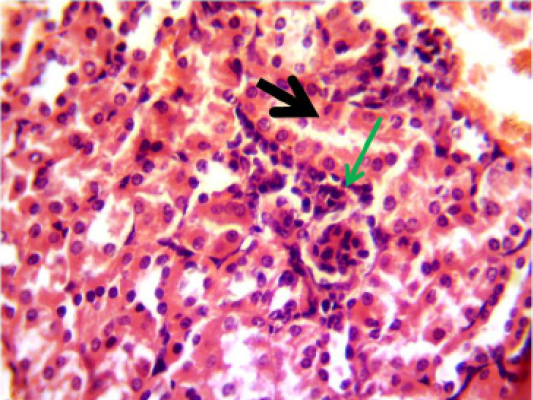

Histopathological section in the kidney of animal feeding B-glucan at 6 weeks post-adminstration with sumithrin shows vacuolar degeneration black arrow and enlargement of epithelial cells of renal tubules wth mononuclear cells infiltration around glomerula green arrow (H and Estain 40X)